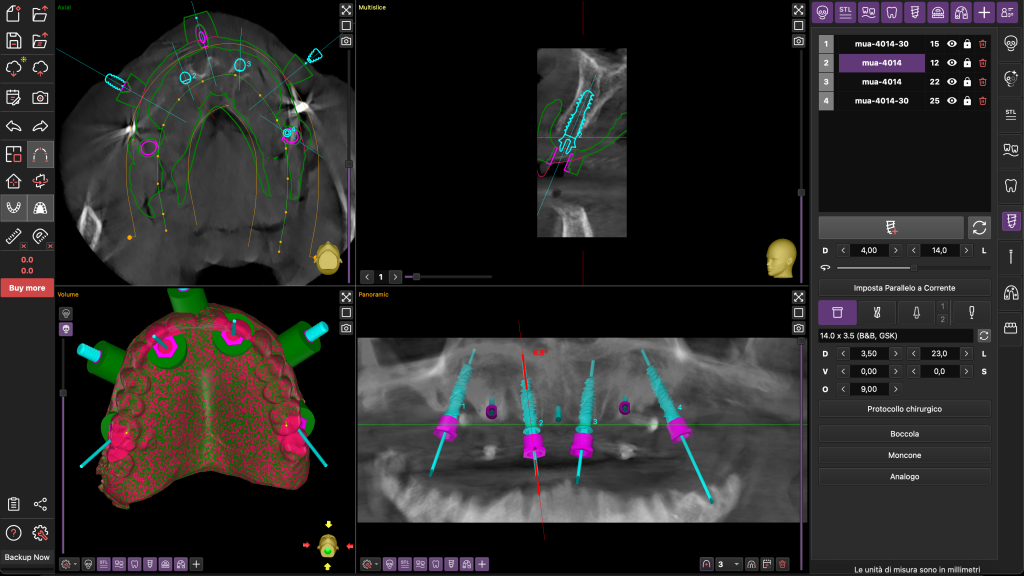

I file STL sono stati poi sovrapposti ai file DICOM della TC Cone Beam con un software dedicato di progettazione guidata B&B Dental. Tramite questo software di chirurgia guidata è stata stabilita la posizione degli otto impianti, da posizionare con l’ausilio di una dima chirurgiche a supporto mucoso fissata con tre pin ossei (Figure 3-4).